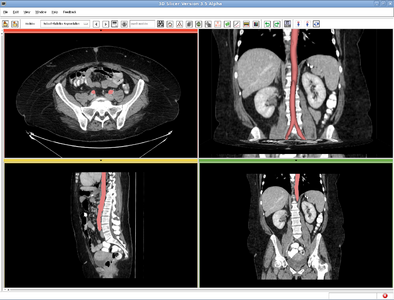

RobustStatisticsSegmentation

Robust Statistics Based Segmentation

Given a few initial seeds, we use the robust statistics to construct a feature image out of the original image, and the image segmentation is carried out in the feature image. To do so, we first compute the certain robust statistics, such as the median absolute deviation(MAD) and the interquartile range (IQ), from the seed points. Further, a multi-dimentional probability distribution function is computed from the feature seeds. At each point in the image, the active contour is driven by the probabilities of this pixel belonging to each category indicated by the seeds.

CLI module in 3D Slicer, in the category of Segmentation